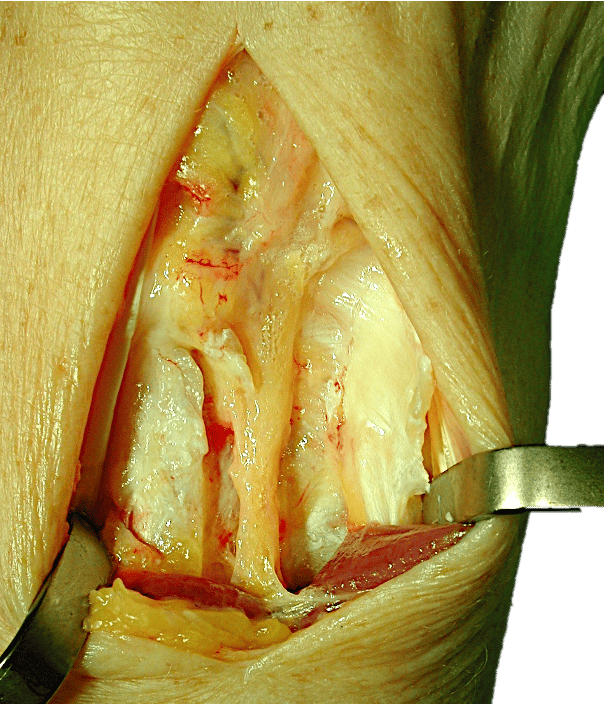

En este abordaje dorsal de la muñeca podemos ver un NIP de características normales, a la altura del tubérculo de Lister, proximal a la articulación radiocarpiana.

Aspecto de un NIP engrosado y degenerado en paciente con sinovitis crónica de muñeca secundaria a proceso degenerativo. Compáralo con la primera imagen.

Este NIP es afuncional y puede ser fuente de dolor.